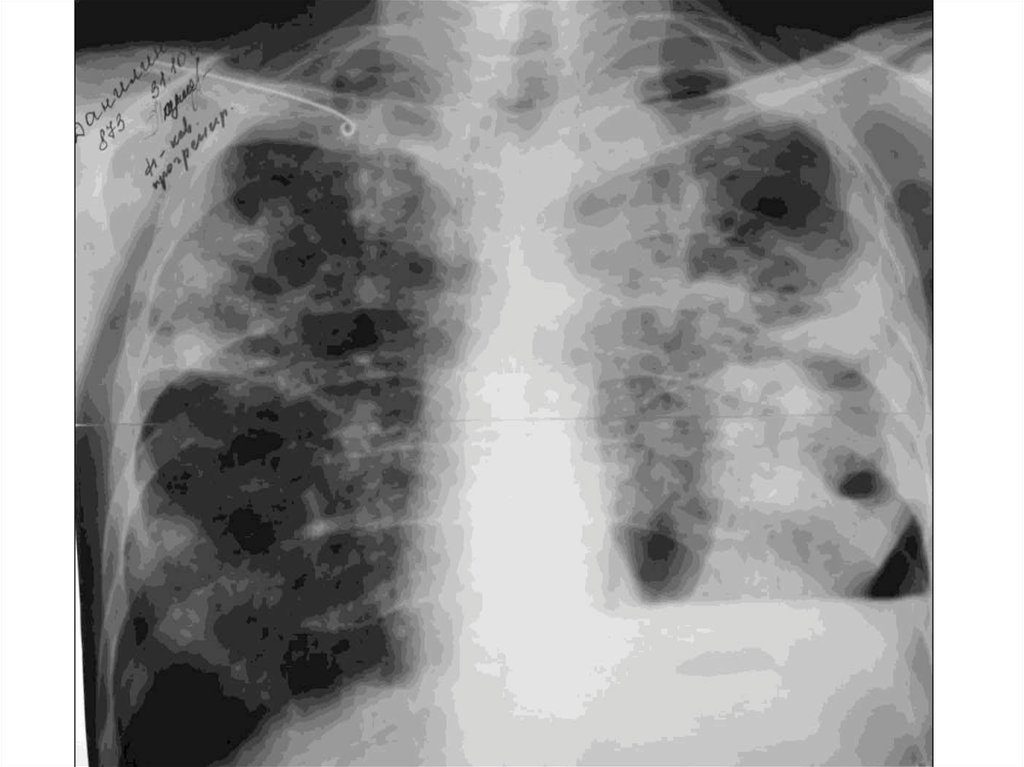

Иллюстрации по теме очагового и инфильтративного туберкулеза

Раздел: Фотодневник открытий